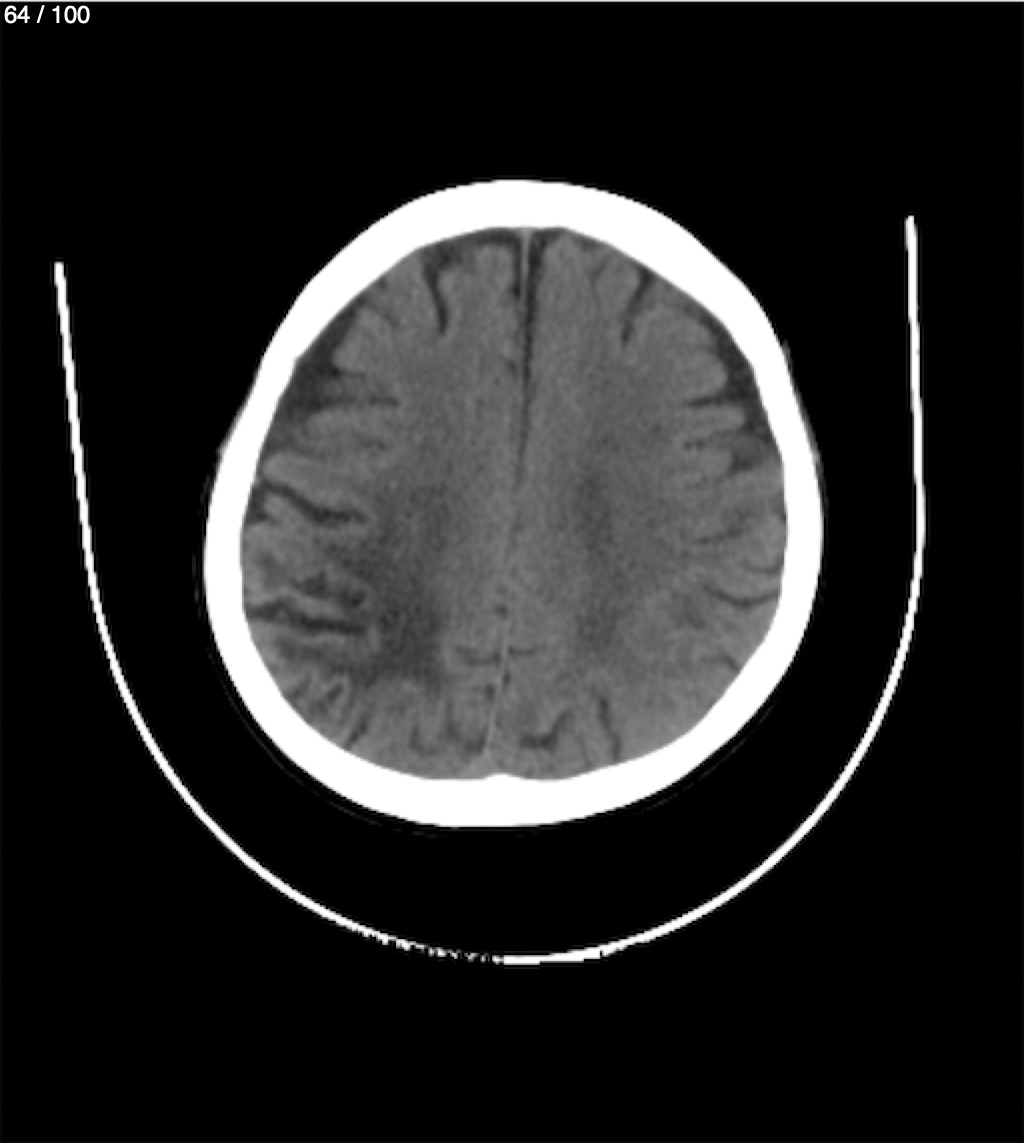

Catarino Perez Escobar 85A - T.C Craneo